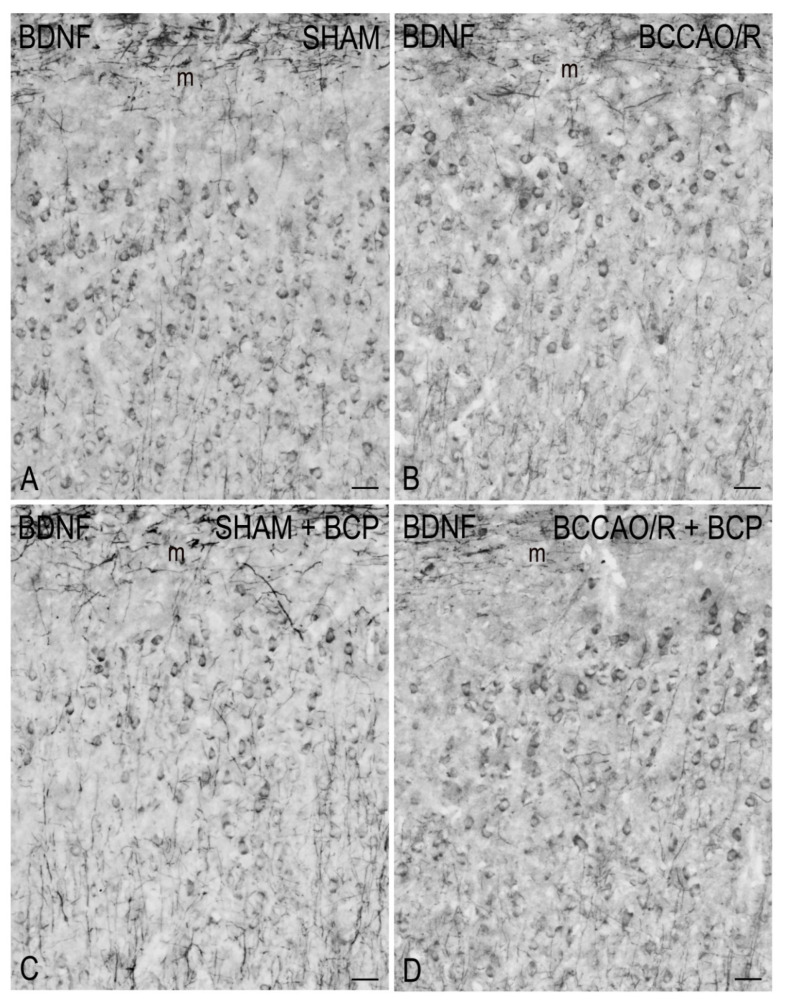

To draw a parallel of the molecular changes observed by Western blot analysis with the tissue morphology, we performed immunostainings of the rat brain sections with the same antibodies used for Western Blot analysis. Immunoreactivities for all examined markers were localized to neuronal structures distributed throughout the rostro-caudal extension of the brain (Figure 3, Figure 4, Figure 5 and Figure 6). As regards the frontal cortex, TRPV1-LI appeared as sparse dot-like elements and tiny varicose nerve fibers distributed mostly close to blood vessels or around them (Figure 3 and Figure 6A,D,G). Neuronal perikarya showing a faint intracytoplasmic staining with a dust-like aspect were further detectable (Figure 6A,D). Labeling of the meningeal lining of the cortex was also detectable. By contrast with the scarcity of TRPV1-LI, the BDNF- and trkB-like immunoreactive structures were numerous and identifiable as neuronal perikarya and proximal processes and nerve fibers distributed throughout the cortical layers, having the aspect of loose networks of thin filaments and punctate elements in the superficial layers, and straight neuronal processes with a prevalent radial orientation in the deep layers (Figure 4 and Figure 5). Double labeling for either TRPV1 and GFAP (astrocyte marker) or TRPV1 and Iba1 (microglia marker), carried out by means of indirect immunofluorescence in selected series of brain sections from BCCAO/R rats showed that, in both BCP- and vehicle-treated rats, rare TRPV1-labelled nerve fibers and dot-like elements were also GFAP-immunoreactive (Figure 6C,F), whereas TRPV1/Iba1 colocalization was virtually absent (Figure 6B).

3.3. BDNF and trkB in BCCAO/R without and after BCP

In the vehicle-treated rats, the ANOVA analysis of frontal cortex homogenates after 30 min of BCCAO followed by 60 min of reperfusion revealed no statistically significant change of BDNF relative protein levels. It has to be taken into account that though not resulting as statistically significant with the post-hoc test, as previously reported [ref. 20], there was a slight reduction of BDNF relative levels in the BCCAO/R rats compared to the sham animals. So far, no studies regarding the acute BCCAO/R-induced changes of mature BDNF protein in the brain cortex at times earlier than 2 h are available. Our findings appear consistent with an earlier study investigating the BDNF protein expression levels in the neocortex in a rat model of 10 min of BCCAO with hypotension followed by 2 h of reperfusion and reporting that low basal expression of BDNF protein further reduced at 24 h [ref. 85]. Interestingly, in their study Kokaia et al. [ref. 85] reported no changes in mRNA expression in the neocortex after the ischemia; this, besides pointing out the importance of analyzing BDNF at the protein level, also led to suggest that the cortex, having low baseline BDNF protein levels, is a region intrinsically vulnerable to ischemia and that BDNF, though decreasing during the 24 h, can play a neuroprotective role after the BCCAO/R challenge. To confirm this inferring, it could be relevant that in our experimental setting the trkB relative levels underwent a concomitant increase that may help assure adequate BDNF trophic signaling. Accordingly, upregulation of the trkB mRNA has been reported after severe ischemia [ref. 85,ref. 86,ref. 87,ref. 88].

Our results showed that the BCP administration, in both sham and BCCAO/R rats, had effects on BDNF, inducing a general decrement of its levels, and on trkB, causing an increment of its expression. It is tempting to speculate that the relative levels of trkB and its ligand complement each other to confer resistance and/or reduce brain damage following the BCCAO/R in vehicle-treated animals. Interestingly, after the BCP treatment, a marked increase of trkB relative levels occurred in the BCCAO/R as compared to sham rats, while BDNF was unchanged in the same conditions. This mismatch leads to envisaging alternative ways of trkB activation, other than the ligand-dependent one, possibly induced by the interaction of the trkB with products of the complex molecular network induced by BCP. In this line, evidence shows that CB1 receptors can couple and transactivate receptor tyrosine kinases and serine-threonine kinases, like ERK, in cultured murine neuronal cells [ref. 89]. Moreover, it has also been shown that CB1, upon activation of AEA and 2-AG, can couple to trkB and trigger the Src kinase-dependent trkB transactivation during morphogenesis of cortical interneurons [ref. 90]. Interestingly, the CB1-trkB coupling had been demonstrated not to involve the increases of BDNF synthesis and/or translation [ref. 90]. In another recent study, AEA and 2-AG, in a CB1- and TRPV1-dependent fashion, trigger a coordinated activation of trkB: the activation of CB1 being crucial for trkB coupling and transactivation in inhibitory cortical interneurons, while the activation of TRPV1 triggering the BDNF release and subsequent activation of trkB in pyramidal cells [ref. 91]. Since, using the same BCCAO/R model, we have previously shown that in the BCCAO/R rats BCP treatment induced the up-regulation of CB1, CB2, and PPARalpha [ref. 18], it is tempting to speculate that the increase of trkB levels in the BCP-treated BCCAO/R rats is subject to the CB1 coupling and transactivation. It is also relevant that BCP may reduce the ischemic injury in rat cortical neurons/glia mixed cultures subject to oxygen-glucose deprivation/re-oxygenation via CB2-induced activation of the AMPK/CREB pathway [ref. 92] and subsequent increased expression of the BDNF, a known CREB target gene product.